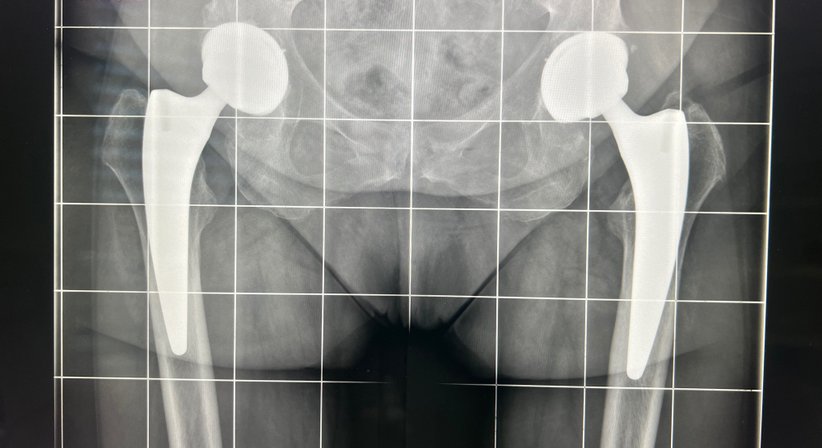

Hüftendoprothetik / HTEP

bei Arthrose des Hüftgelenks / Coxarthrose und Ausschöpfen der nicht operativen Therapie